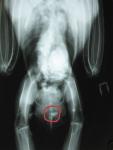

air-bird Опубликовано 6 октября, 2009 #54 Опубликовано 6 октября, 2009 Ноги чувствуют все - все сжимает, даже пытается стоять. Только что прощупал получше хвост и... вобщем боюсь он действительно упал сильно.На участке там где рули входят в хвост обнаружил какой-то неестественный нарост типа черяка размером 10 мм высотой и 10 в радиусе, а рядом что-то вроде надрыва. Крови нету. Хвост он поднимает когда ходит по нужде, но как-то слабо, но совсем не может расправлять перья.Вот место:

air-bird Опубликовано 6 октября, 2009 #56 Опубликовано 6 октября, 2009 А я то про железу совсем забыл! =)))Но меня это все заставило пересмотреть рентген и кое-что может быть интересным: